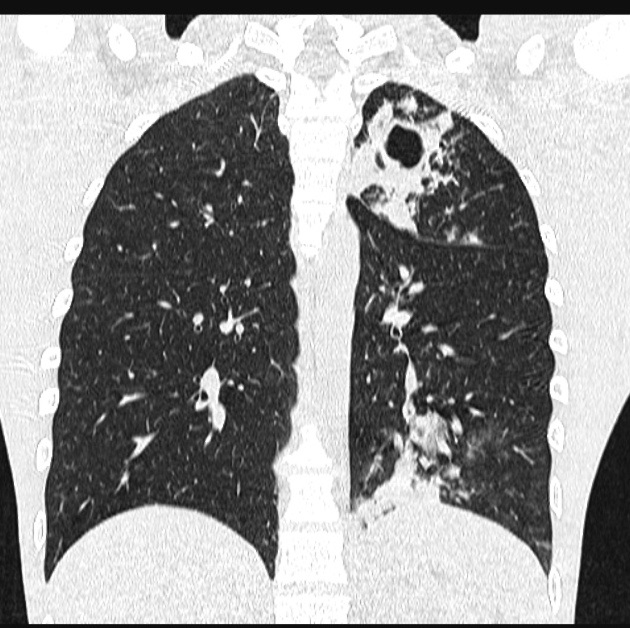

bambou ». À pulmonaire, il peut exister une

dystrophie bulleuse après plusieurs décennies d'évolution ,

ou une fibrose pulmonaire

Image radiologique PA

d'une fibrose pulmonaire avec aspect de fibrose de